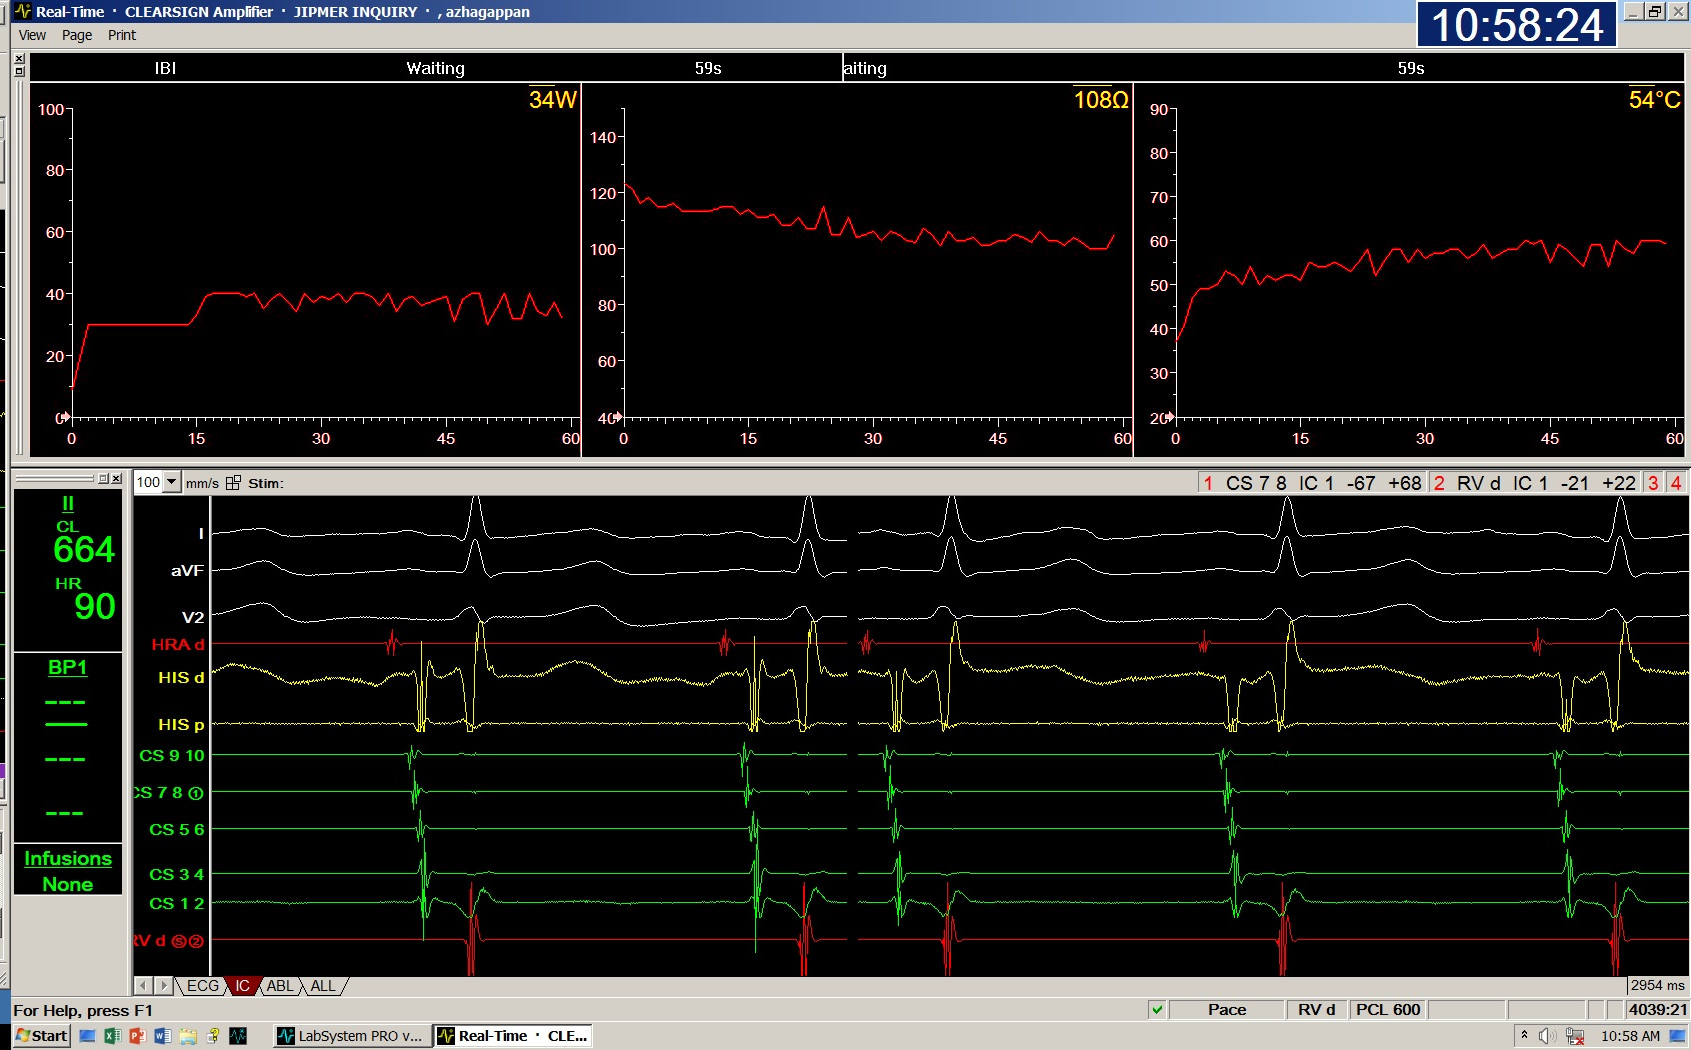

RF parameters to identify effective ablation

RF Parameters.jpg